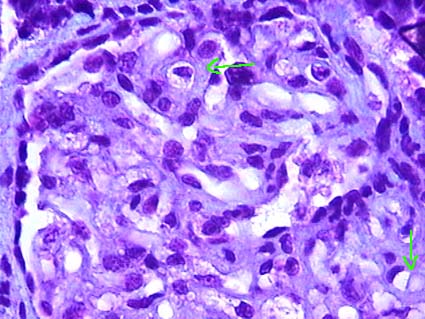

Polyarteritis nodosa (PAN): Vascular lesions are localized in medium-sized vessels: interlobar, arcuate and interlobular arteries. In the same biopsy it is frequent to find lesions in different stage: acute and chronic. In the active phase there is fibrinoid necrosis in segments of the artery, with leukocyte infiltration; in early phases predominate neutrophils which fragment in the arterial wall: leukocytoclasia, subsequently neutrophils are replaced by lymphocytes, monocytes and macrophages. The necrosis begins on the inside of the artery wall and can be transmural, affecting non continuous sections, so that sometimes it may not be easy to find; it is most often located at the bifurcation of the arteries. Fibrinoid necrosis is eosinophilic with H&E and red with trichrome stains and is accompanied by karyorrhexis and destruction of the internal elastic lamina (Figure 16). We can detect thrombi in areas of necrosis, which can lead to cortical infarctions that appear triangular. Nodules that give the name to the disease are areas of vasculitis with inflammation around, they are more frequently seen in the skin, but they can be seen in other organs such as the kidney. In some cases there are aneurysms due to arterial wall destruction (also originate nodules). In the chronic stages of injury there is vascular sclerosis, recanalization of thrombus and organization of the injured tissue, this can lead to renovascular hypertension. In cases where we only found adventitial inflammation we cannot diagnose PAN, it is necessary to demonstrate the acute lesions of vasculitis.

Figure 16. Cortical radial artery with fibrinoid necrosis of its wall (blue arrows) and inflammatory cells in the middle of this fuschinofílic material (red). Green arrows indicate arterial wall segments without lesion and asterisks the vessel lumen (Gomori’s trichrome stain, X400).